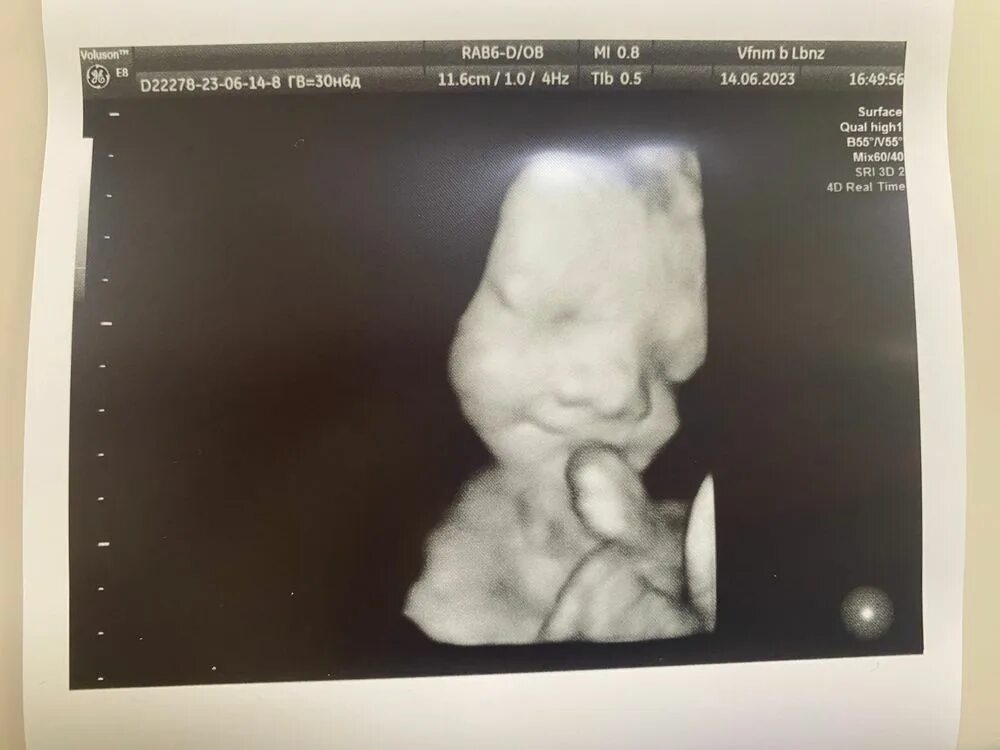

Хороший второй скрининг форум